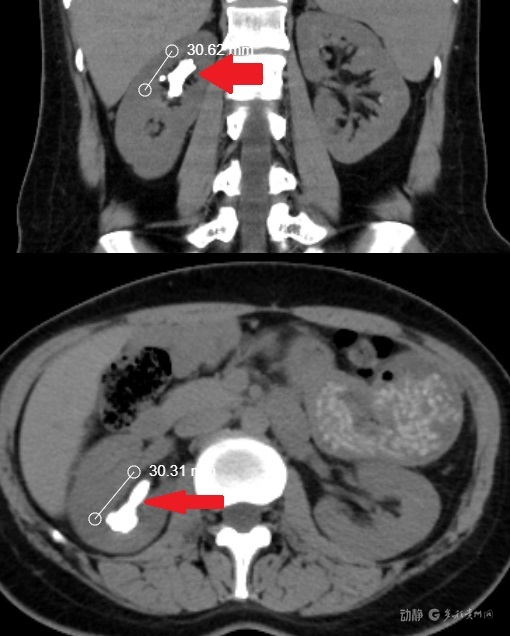

据了解,患者是一名青年女性,右肾内藏有一枚长径、宽径均达3公分的柱形结石,属于复杂高危的大体积结石,平日里时常感到腰腹隐痛,严重影响了正常生活。更让她纠结的是,因格外在意身体外观,担心传统手术留下永久疤痕,她此前辗转多家医院就诊,每次听到医生告知需行经皮肾镜打洞取石,内心的恐惧与顾虑就让她迟迟无法下定决心,手术一事一拖再拖,结石问题也始终悬而未决。

术后即刻复查CT显示,患者体内结石清除率接近100%,真正做到“片石不留”,仅需留置常规引流管与输尿管支架,肾脏形态恢复良好。恢复期间,医护人员每日定时查房,细致叮嘱她饮食、饮水和活动的相关禁忌,关注她的每一点身体变化。得益于无创手术的优势,患者恢复速度远超预期,术后第二天便已能正常下床活动,身体无明显不适,顺利办理出院。